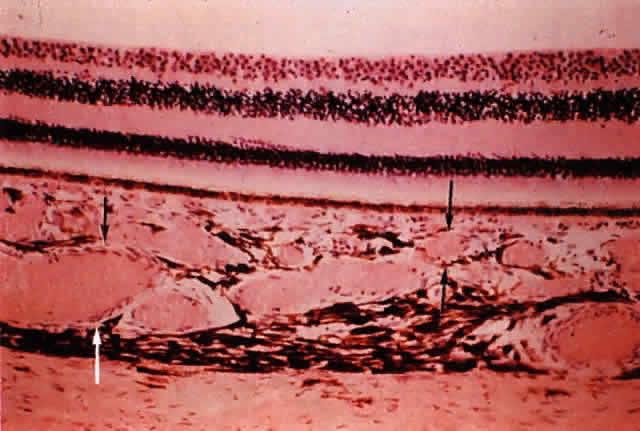

Fig. 4. Choroid. Middle layer of medium-sized vessels (Sattler's layer, between two black arrows); outer layer of large vessels (Haller's layer, between black and white arrows). (H & E, × 125)

The deep brown color of the choroid results from the large number of melanocytes found around the noncapillary blood vessels in the deeper layers of the choroidal stroma and in the suprachoroidal lamellae. The number of melanocytes in the choroid increases from the inner to outer layers. The choroidal vasculature can be visualized in albino patients because of their lack of melanin pigment (Fig. 5). The vascular pattern may also be observed on gross examination of eyes (Fig. 6).